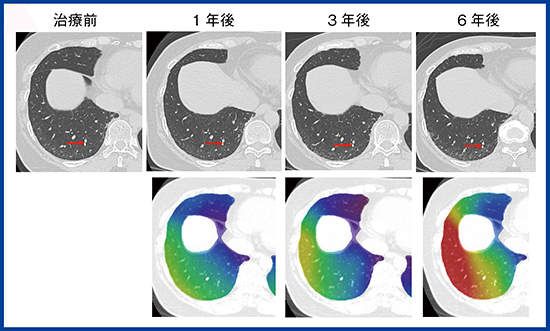

肺は,正常では体積の80%が空気である。したがって,線維化とともに虚脱が起こると,正常肺の減少に比較して,病変の容積増加は少ない7)。特にUIPパターンの線維化では,初期には胸膜に張りつくように線維化が起こるため,虚脱した肺が胸膜と一体となってCTでは認識しづらい。QZIP-ILDのような定量解析を行っても,虚脱を伴う線維化では体積が1/5に減少するため,病変の増加はごくわずかで,疾患進行を見逃しやすい。しかし,線維化自体は見えなくても,局所の肺の構造のゆがみは起こっている11)。CTを注意深く観察すると,UIPでは末梢の血管が徐々に胸膜に近づいていくのがわかる(図4上段)。

われわれは,この肺の末梢構造のゆがみを移動量として計測することにより,肺内で起こっている線維化を検知できないかと考えた。この移動量を可視化するため,非剛体位置合わせを利用した手法をザイオソフト社と開発した。非剛体位置合わせは,呼吸による位置ズレがある胸部では,例えば単純CTと造影CTを重ねる際などに現在広く行われている手法である。通常は位置ズレを補正して2枚の画像を重ねるが,今回は各ポイントの位置のズレを移動量として元画像に重ねて,カラーマップで表示した(図4下段)。カラーマップにより,わずかな血管の位置移動が把握しやすくなると考えている。この手法を用いて,IPF 41症例について,肺の内側,外側1cmの領域に分けて病変の容積と移動量を測定したところ,線維化病変は肺の外側に多く,移動量も外側に多いことがわかった12)。本手法の有用性について,今後,さらなる検討を重ねたい。

図4 50歳代,女性,特発性肺線維症(IPF)

CT画像と移動量のカラーマップ表示。QZIP-ILDによる病変の体積は初診時2.5%, 1年後3.0%,3年後3.9%,6年後4.4%とわずかに増加していたが,肺全体の容積減少はわずかだった。CTの元画像では胸膜下の血管がだんだんと胸膜に近づいている(→)。移動量では下葉背側末梢を中心に大きな移動を示す赤色が広がっている。